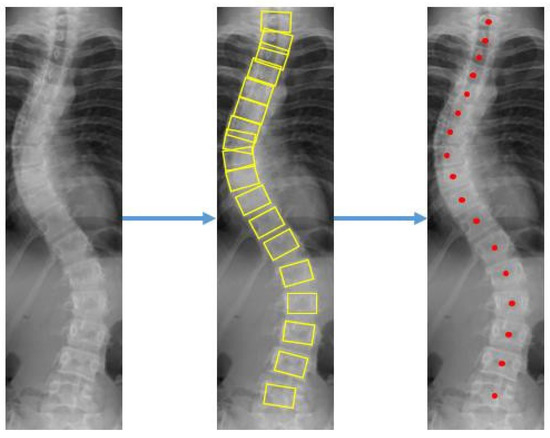

The center offset and corner offset maps using convolutional layers for landmark localization were constructed. Since the output of the feature map on the network is downsized, the center offset and corner offset are mapped to a new location which is then trained with L1 loss. Detection bounding boxes were displayed on each vertebra after applying the object detection step on the X-ray images. The coordinates for the corners and center of each bounding box were found as presented in Figure 6.

Figure 6.

Progressive results of the vertebrae detection to get the location of 4 corners and a center.